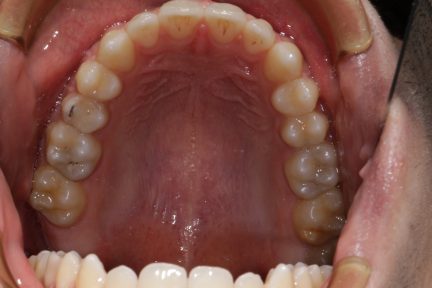

Classe III, articulé croisé antérieur, béance, espacement, diastème

État initial